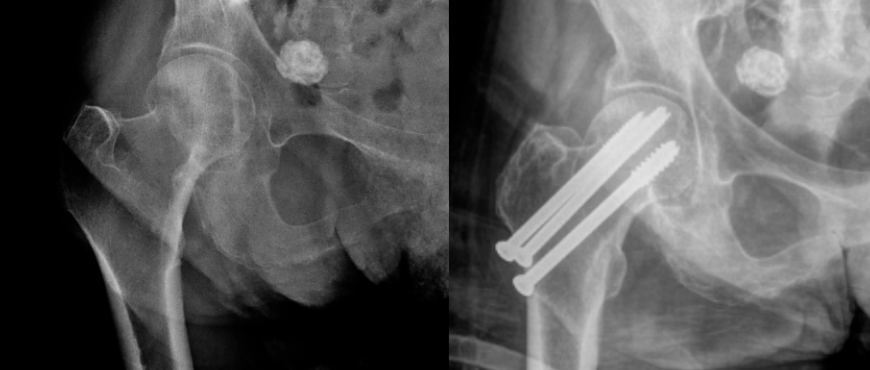

股骨粗隆间骨折(又称股骨转子间骨折)是髋部骨折的常见类型,多发生于骨质疏松的老年人群。随着社会老龄化加剧及人均寿命延长,此类骨折的发病率呈显著上升趋势。其主要诱因为下肢突然扭转或跌倒时局部应力集中,导致股骨近端转子间骨质断裂。治疗的临床挑战包括术中出血量大、术后死亡率高、内固定失效风险、畸形愈合倾向。

根据Evans-Jensen或AO分型判定骨折稳定性,稳定性骨折可选动力髋螺钉(DHS),复杂型需采用股骨近端防旋髓内钉(PFNA)等髓内固定系统。

结合骨密度、骨折线走向选择内植物,如骨质疏松者优先选用具有螺旋刀片的PFNA以增强把持力。

术中需通过C型臂多角度透视确保颈干角恢复至130°±5°,主钉进针点严格位于大转子顶点,避免医源性骨折扩展。